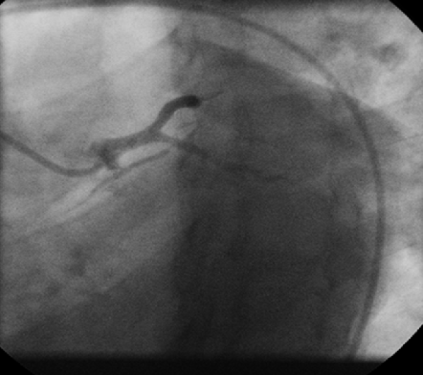

Six weeks after PCI, this patient presented with progressively worsening angina over a two-week period. A repeat angiogram was performed, in anticipation of significant restenosis and it showed an unexpected result, revealing critical disease in ostial left main and patent stents (Figures 2 and 3). Urgent CABG was recommended, but patient refused to undergo surgery. Risks of PCI to left main coronary artery were explained in detail. A 7 French JL 4 guide catheter was selected and guide wire was advanced into distal LAD. Left main lesion was predilated with a 3x13 mm Nimbus Salvo balloon (Clear Stream Technologies Ltd. Wexford, Ireland) and a 4x16 mm (BMS) Clear flex (Clear Stream Technologies Ltd. Wexford, Ireland) was deployed in proximal left main at 18 ATM and post dilated with a 4.5x18 mm Power Sail complaint balloon (Guidant, corporation, Santa Clara USA). End result was successful with TIMI 3 flow distally without any complications. The patient incurred no complications following the procedure.

Figure 3: LAO caudal view showing critical disease in body of left main coronary artery (Case 1).